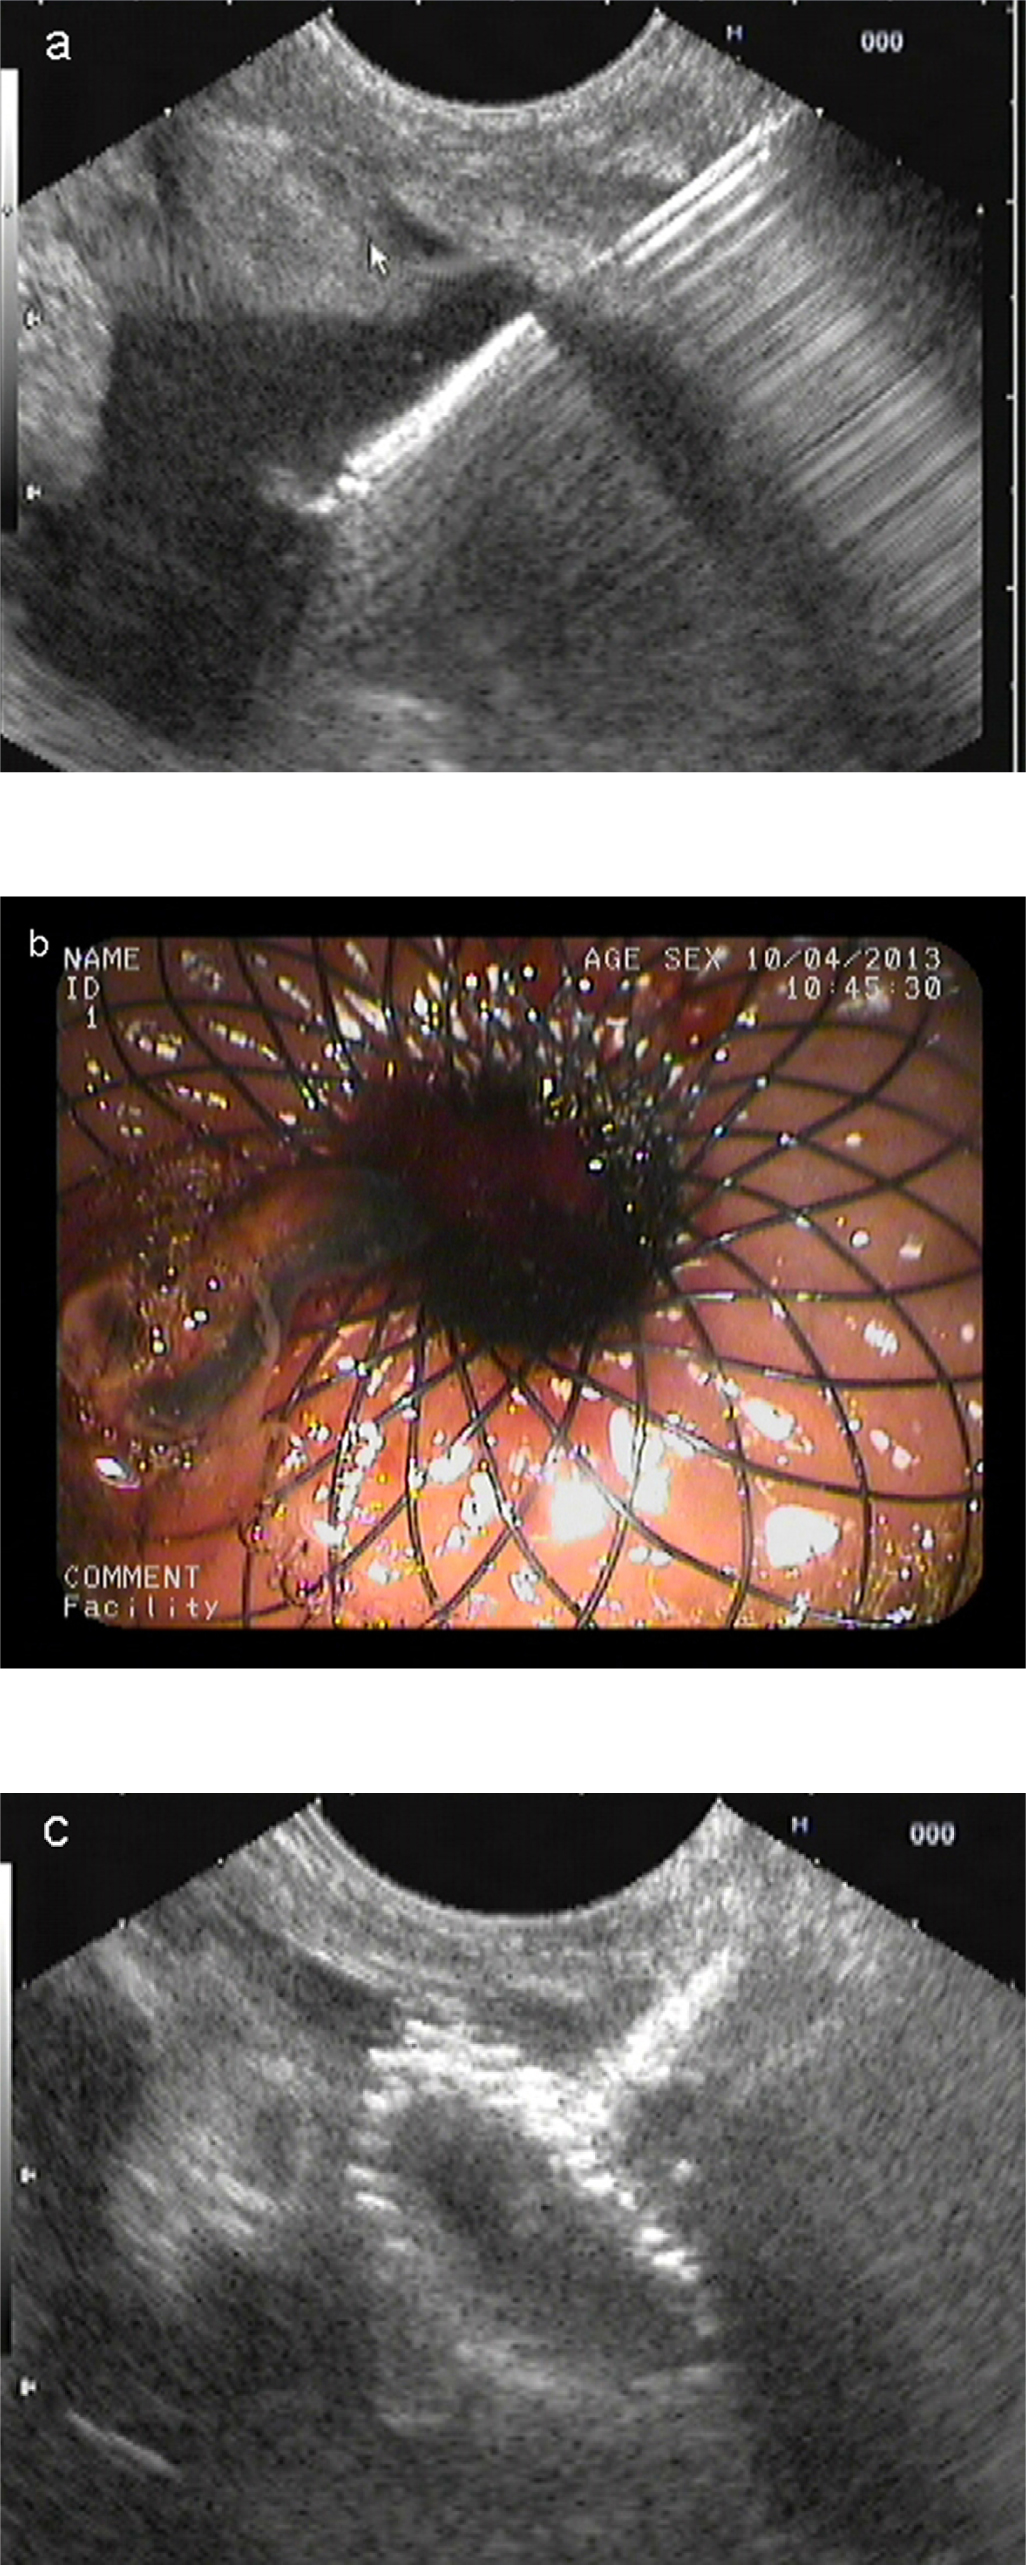

EUS-guided drainage process with metal stent

The initial steps were the same as the plastic stent placement. After the needle path was dilated by the cystotome, the stent (10 mm/35 mm; Micro-Tech/Nan Jing CO., Ltd.) was slowly deployed into the cyst under the guidance of EUS until the distal flared end was completely open (Figure 2). Gentle traction was applied to pull the cyst wall close to the gastric wall. Then, under endoscopic surveillance, the remainder of the stent was deployed, keeping the proximal end in sight. The stomach was irrigated with saline, and EUS scanning was used to confirm the position of the stent and rule out further leakage. In some cases, a doublepigtail stent (PE double-pigtail 10 Fr/7 cm, 10 Fr/3 cm or 10 Fr/5 cm, ENDO-FLEX GmbH, Germany) was introduced through the metal stent for auxiliary drainage.

Endoscopic ultrasound (EUS)-guided drainage process with metal stent. (a) EUS-guided cyst puncture with needle; (b) endoscopic image of the metal stent; (c) EUS image of the metal stent.